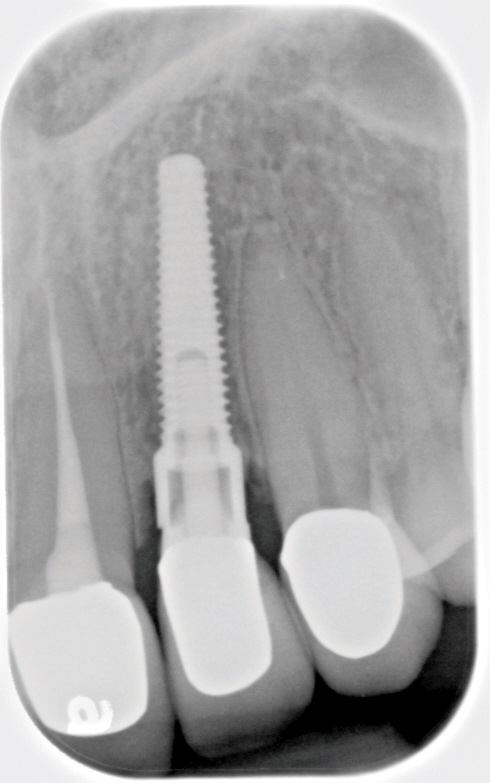

Fig 6. Radiograph following crown fracture.

Fig 7. Ill-fitting milled abutment obtained from a third-party vendor and not from the manufacturer.

Fig 8. Loss of restoration and subsequent tissue overgrowth from broken abutment screw as shown in the radiograph (Fig 9).

Fig 9. Radiograph depicting fractured screw inside of the implant.

The use of third-party vendors for prosthetic components should be avoided.10 Third-party components (Figure 7) typically do not fit to the same standards as the manufacturer’s recommendations and can, thus, both weaken the screw connection before the screw is even placed in function and introduce micromotion that may lead to fracture of the implant or the screw/prosthesis, or crestal bone loss.11,12